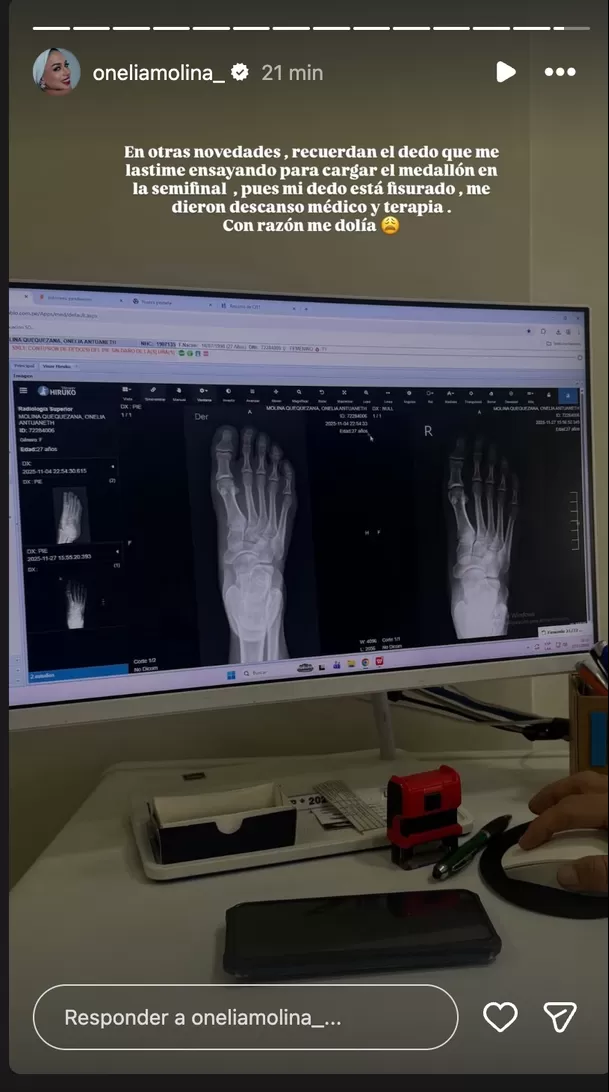

Onelia Molina sorprendió a sus seguidores al revelar que tiene una fisura en uno de los dedos del pie.

La competidora de “Esto es Guerra” publicó en sus redes una imagen de su radiografía y contó que la lesión ocurrió durante los ensayos para la semifinal del programa.

Según explicó en su historia de Instagram, todo sucedió mientras practicaba una de las cargadas del famoso medallón.

“Me dieron descanso médico y terapia”, escribió Onelia junto a la imagen de la pantalla donde se observan sus radiografías.

“Con razón me dolía”, agregó en el mensaje, dejando ver que el malestar venía de días atrás. La lesión fue diagnosticada como una fisura ósea y, por recomendación médica, deberá guardar reposo.